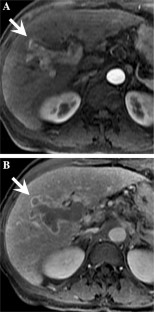

Fig. 2